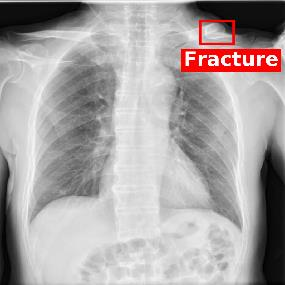

Chest X-ray (CXR) is the most typical diagnostic X-ray examination for screening various thoracic diseases. Automatically localizing lesions from CXR is promising for alleviating radiologists' reading burden. However, CXR datasets are often with massive image-level annotations and scarce lesion-level annotations, and more often, without annotations. Thus far, unifying different supervision granularities to develop thoracic disease detection algorithms has not been comprehensively addressed. In this paper, we present OXnet, the first deep omni-supervised thoracic disease detection network to our best knowledge that uses as much available supervision as possible for CXR diagnosis. We first introduce supervised learning via a one-stage detection model. Then, we inject a global classification head to the detection model and propose dual attention alignment to guide the global gradient to the local detection branch, which enables learning lesion detection from image-level annotations. We also impose intra-class compactness and inter-class separability with global prototype alignment to further enhance the global information learning. Moreover, we leverage a soft focal loss to distill the soft pseudo-labels of unlabeled data generated by a teacher model. Extensive experiments on a large-scale chest X-ray dataset show the proposed OXnet outperforms competitive methods with significant margins. Further, we investigate omni-supervision under various annotation granularities and corroborate OXnet is a promising choice to mitigate the plight of annotation shortage for medical image diagnosis.